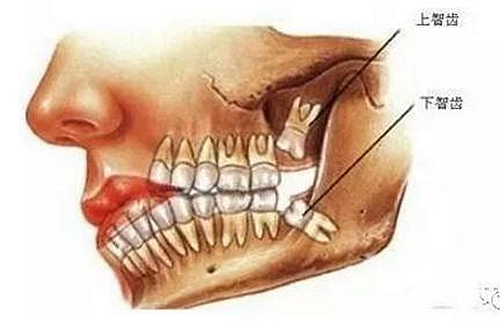

智齒也稱智慧齒、是人類的第三磨牙,隨著遺傳基因的不同智齒一般會(huì)在16-30歲之間長出,也是人一生中最后長出的牙齒,所以它最靠近喉嚨,因?yàn)榇藭r(shí)期的人們心智比較成熟而得名。從門牙數(shù)往里第八顆,一般成年后長出來。由于人類進(jìn)化,這顆第三磨牙失去了作用。逐漸退化,限制于空間,有些長歪了,有些頂著前面的牙齒,有些埋伏在牙槽骨里出不來。

智齒周圍是牙槽骨,前面緊挨著第二磨牙,智齒下方大約兩三毫米遠(yuǎn)有一下頜神經(jīng)管,這神經(jīng)主要是下頜牙齒及下唇部位的知覺神經(jīng),一旦斷了,就會(huì)失去知覺。